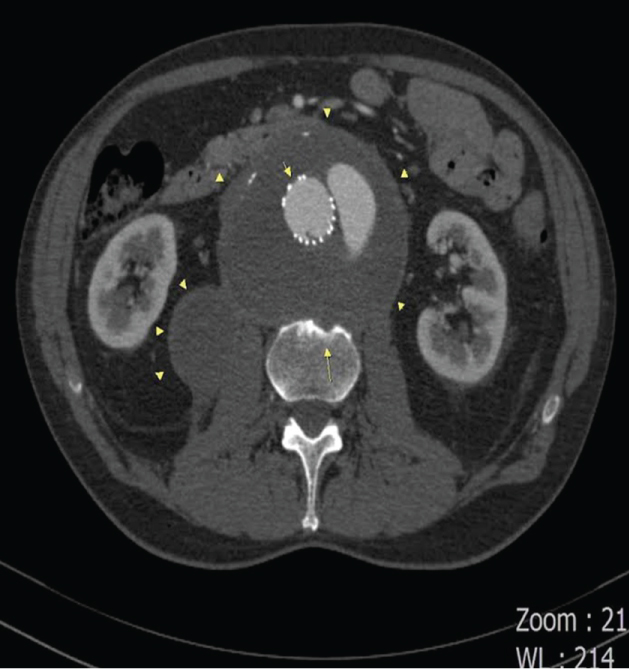

Case 1: A 71-year-old man with low back pain for more than a year, cortical erosion and vertebral cyst formation of L4 vertebral body were diagnosed on lumbar MRI. There was no compression fracture or bone marrow edema. The fusiform unruptured aneurysmatic dilatation of abdominal aorta was seen adjacent to the vertebral cyst (Figure 1 and Figure 2). The vertebral cyst was thought to be associated with abdominal aortic aneurysm (AAA). The aortic wall defect or paraaortic hematoma was not established. After the diagnosis of AAA associated with vertebral cyst, the patient was referred to cardiovascular surgery.

Figure 2: Axial T2W FSE lumbar MRI image: The vertebral cyst (long arrow) is seen adjacent to the aortic aneurysm (arrowhead). View Figure 2